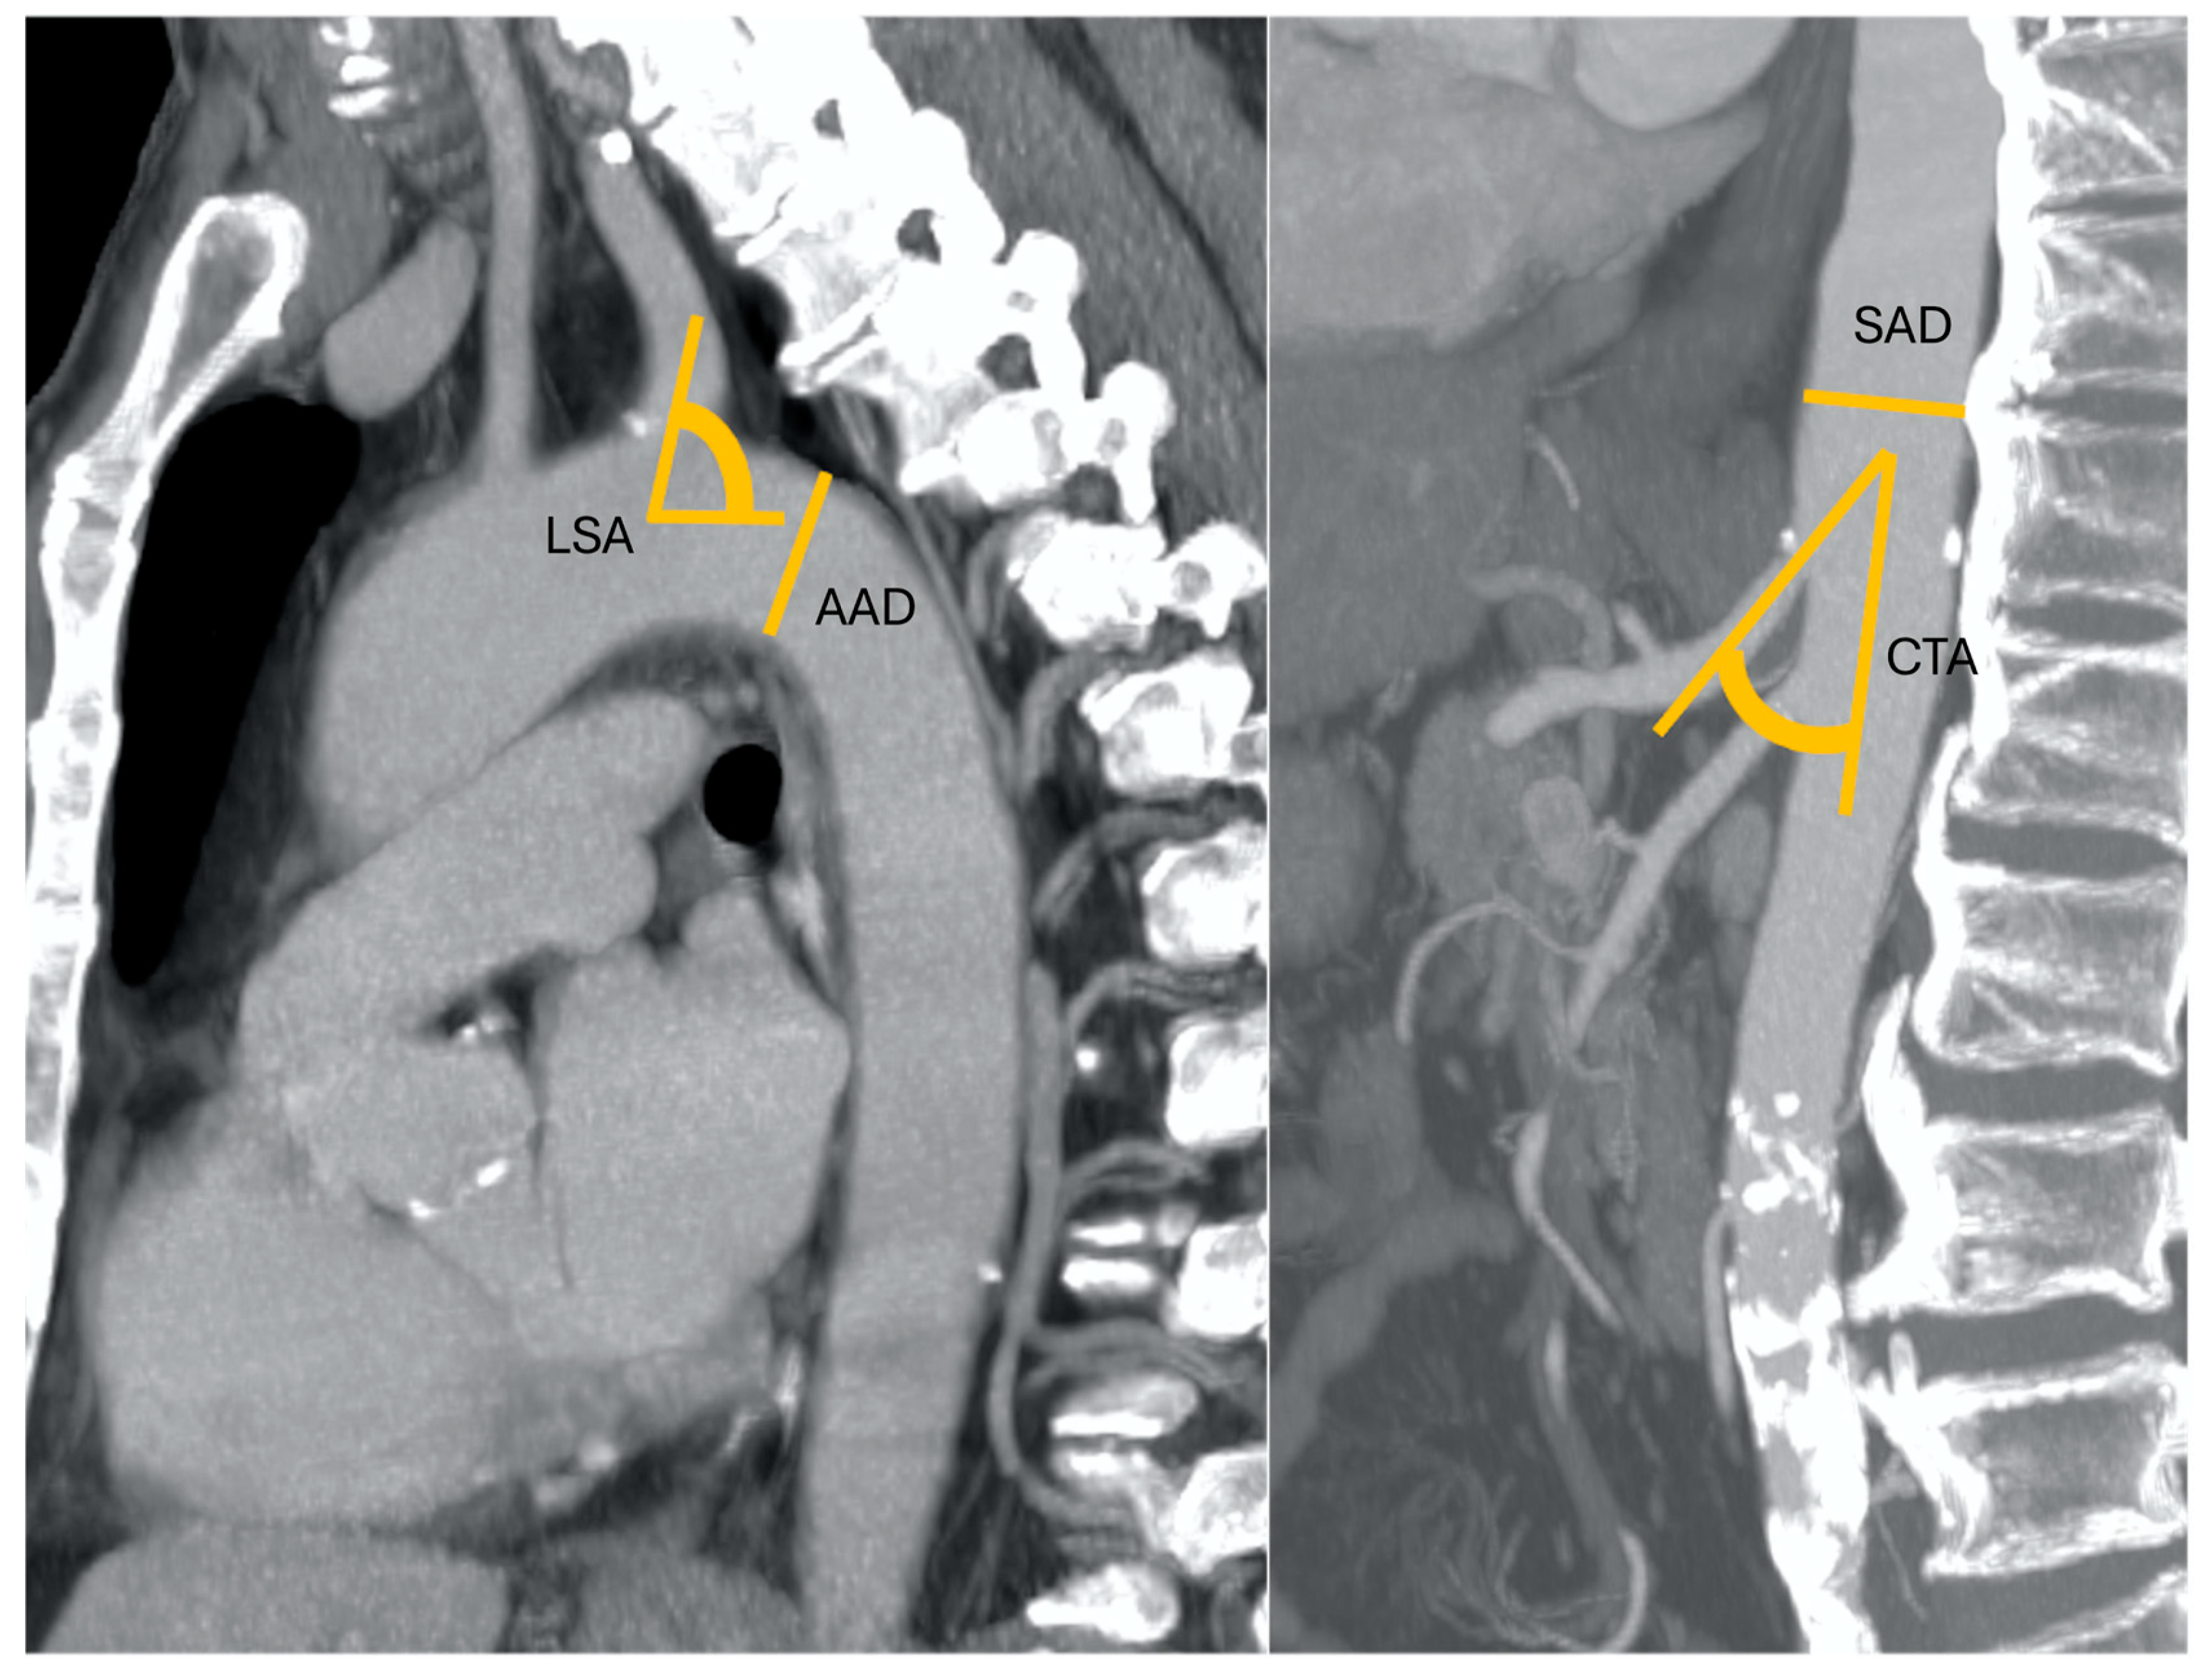

Pre-procedural CT examinations were retrospectively analyzed independently by two radiologists, each one with more than five years of experience in thoraco-abdominal radiology. Readers were blinded to medical history, clinical parameters, and procedural details. The following data were collected for all the CT examinations performed prior to the procedure: aortic arch diameter (AAD, measured at the level of origin of subclavian artery) and angulation (AAA) according to Madhwal and colleagues [8]; left subclavian artery angulation (LSA); descending thoracic aorta diameter evaluated in the proximal tract; angulation of descending thoracic aorta (according to the classification by Belvroy and colleagues [9]; suprarenal abdominal aorta diameter (SAD) measured at the level of origin of celiac trunk; take-off angle of celiac trunk (CTA); anatomical variants of the hepatic artery [10,11]; and previous aortic and periaortic vessel interventions, if any. The data sets of each patient were loaded into a dedicated three-dimensional workstation (Advantage Workstation VolumeShare 4; GE Healthcare, Milwaukee, WI, USA). For length measurements, reformatted cross-sectional images longitudinal to the long axis of the vessel were automatically obtained to create “modified coronal” planes. Vessel segmentation was automatically performed. All measurements of diameters, lengths and angles were manually completed using graphical measurement tools in the post-processing application software. To minimize variability, the two experienced radiologists performed all measurements twice, and the final mean values were considered.

Figure 2. An 83-year-old patient with nodular HCC in the right liver lobe with a radial diameter (RD) of 2 mm (not shown) (0 points), left subclavian artery angle (LSA) of 45° (1 point), an aortic arch angulation (AAA) type III (1 point) with a diameter (AAD) of 32 mm (1 point), suprarenal aorta diameter (SAD) of 40 mm (1 point), and celiac trunk angle (CTA) of 130° (1 point). Final RAD-access score: 5, transfemoral access preferred for values between 3 and 6.